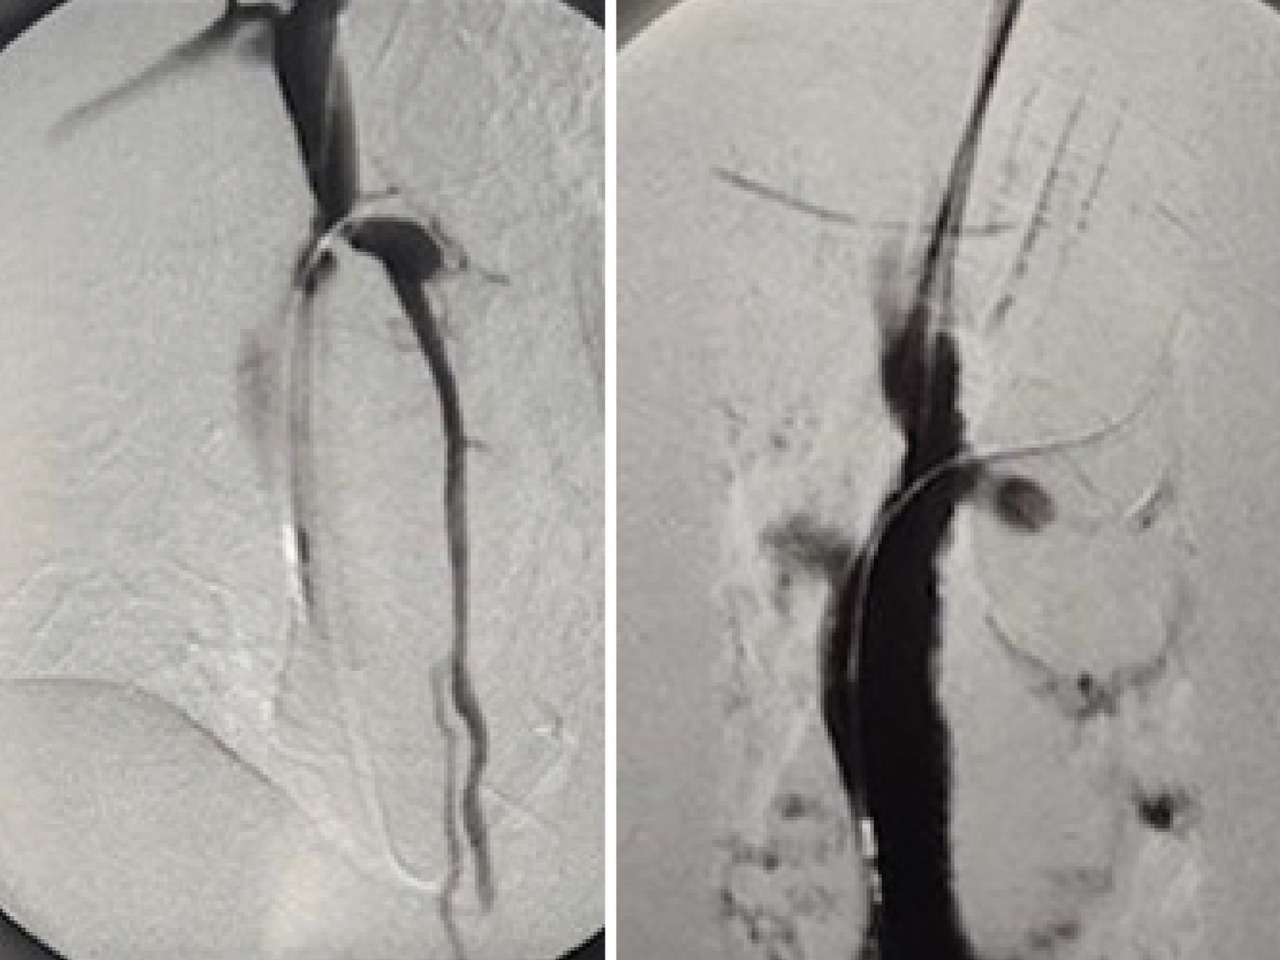

Une tomodensitométrie thoraco-abdomino-pelvienne avec et sans injection est réalisée. Elle retrouve une veine cave sténosée d’aspect très serré (fig. 2), expliquant les varices thoraco-abdominales. Ces dernières servent de réseau de suppléance au système cave supérieur et drainent ainsi la partie supérieure du corps. Le patient est hospitalisé en chirurgie thoracique et cardiovasculaire afin de bénéficier d’une dilatation cave supérieure par voie endoluminale (fig. 3), sans pose de stent.

Les suites sont simples ; le patient rentre à domicile avec une prescription d’apixaban à poursuivre pendant sept jours et de l’acide acétylsalicylique à 75 mg.

Une consultation de suivi réalisée deux mois plus tard ne révèle aucune complication secondaire (fig. 4).